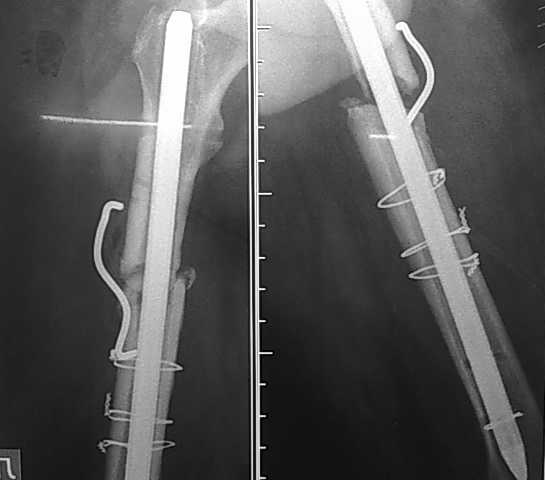

пациент 45 лет имел перелом бедра в 2006г плюс О.инфаркт. после лечения инфаркта - о\синтез стержнями - перелом стержней с миграцией "туда-сюда" в канале кости. далее БИОС 12 стержнем (канал 14). после динамизации синтеза - рецидив болей и патологич.подвижность. ввиду отсутствия конструкций и финанс.положения пациента - реостеосинтез через 2 года ( за это время 3 случая рожистого воспаления голени на этой же ноге) стержнем ЦИТО 14 размера с костной пластикой "чипсами" и фиксацией скобой с памятью формы - результат на Рг-грамме через 3 мес.( вес пациента 120кг). при введении стержня ЦИТО - после рассверливания до 14 диаметра - все равно трещина в дистальном отломке. планируем БИОС 14 гводдем с блокированием в 2х плоскостях и костную пластику из крыла или по Хохутову - НЕТ 14 СТЕРЖНЯ ТИПА ЭКСПЕРТ - НИГДЕ!!да и дорого пациент не может заплатить. Есть ли у кого какие идеи, (пациент намучился, настроен на БИОС - получал консультацию доцента, ДМН.

Но делая закрытый интрамедуллярный остеосинтез, желательно устранить грубые смещения. Для планирования надо бы сделать снимки на протяжении, а также сравнительные (или КТ проксимальных и дистальных отделов) - не надо ли тут устранять ротацию.